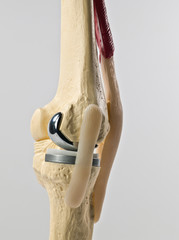

For someone whose knee has become creaky, the method of replacing it with a new, metal-and-plastic version of the joint can be beguiling.

When your normal life is hampered because of the pain, a surgery is required only when the damage is in the last stage or “when the bones are touching each other”, with degeneration and wear and tear having destroyed the cartilage between the bones altogether.